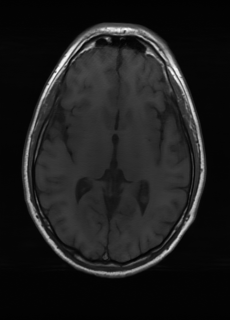

As we observe from the right image in Fig. 2, our BRM, both from MIMO and SISO settings, predicts the performance of dedicated models with a high correlation. We further choose the best three , and perform the last stage of fine-tuning accordingly to (6). A visual evaluation on real data is shown in Fig. 3. For simulated data, please refer to the Supplemental Material section.

Base on the best performing , we perceive that among , , and FLAIR, the results are best when is sampled the most. We suggest that this makes intuitive sense as images provide the best contrast out of the three sequences, which can compensate for the details lost in other images. The same observation can be made on the simulated data, where both and FLAIR show good contrast. When the time setting is changed to non-uniformity, we can see that our search for the best sampling strategy reflects the change. is sampled more as a result of faster acquisition time, while is still sufficiently sampled.